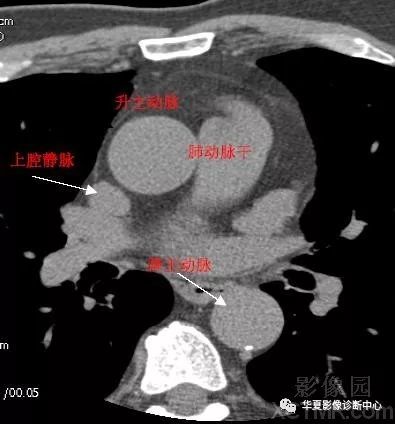

影像解剖|心脏冠状动脉ct解剖中文详细标注(图文)